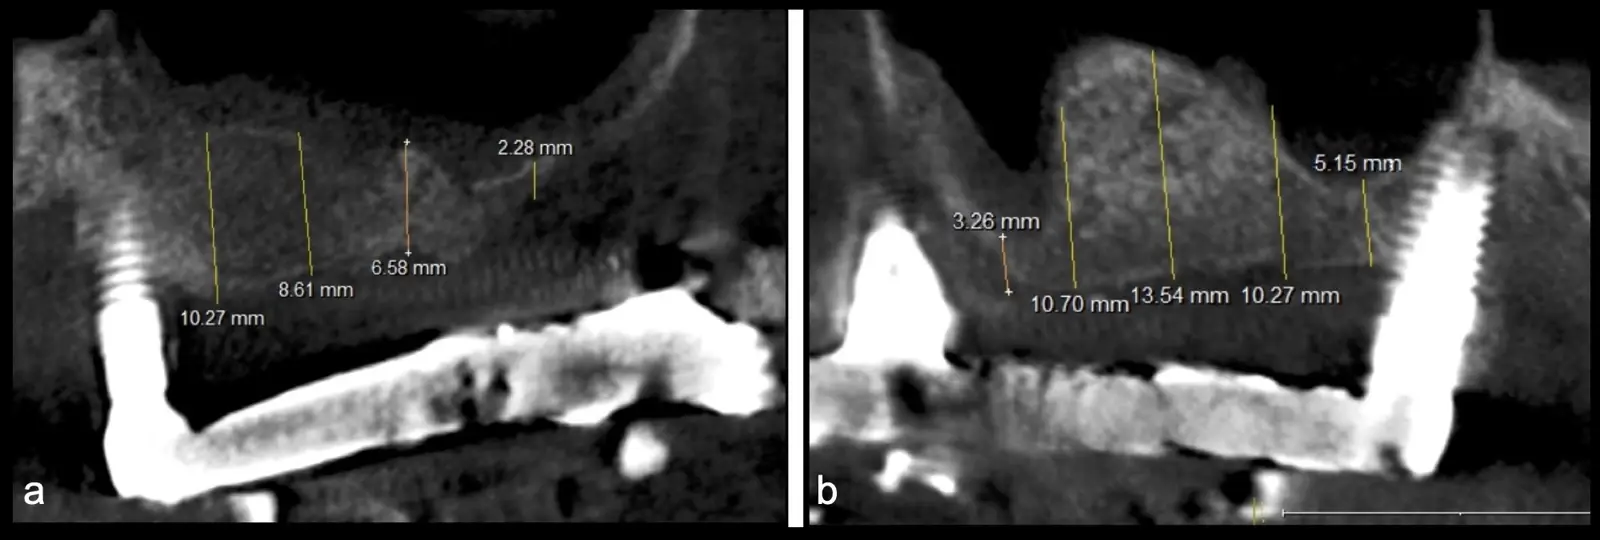

Paciente de 62 años, de sexo masculino, llega a la consulta para la colocación de implantes dentales. Refiere haber tenido tratamiento previo con implantes dentales, algunos de los cuales fueron perdidos. A la evaluación clínica se observa ausencia de piezas dentarias en el maxilar superior y 3 implantes remanentes. En la evaluación tomográfica se observa neumatización de los senos maxilares del lado derecho e izquierdo (Figura 14), para lo cual se indica el procedimiento quirúrgico de levantamiento de piso de seno maxilar en ambos cuadrantes, como paso previo a una nueva planificación implantosoportada.

Figura 14. Evaluación intraoral en donde se evidencia presencia de una prótesis híbrida soportada sobre implantes dentales, al retiro de la estructura se observó tornillo protésico fracturado (a, b, c). Evaluación tomográfica: corte sagital a nivel de los senos maxilares derecho e izquierdo, donde se observa una atrofia severa de los rebordes óseos acompañados de neumatización de los senos maxilar (d, f, g).